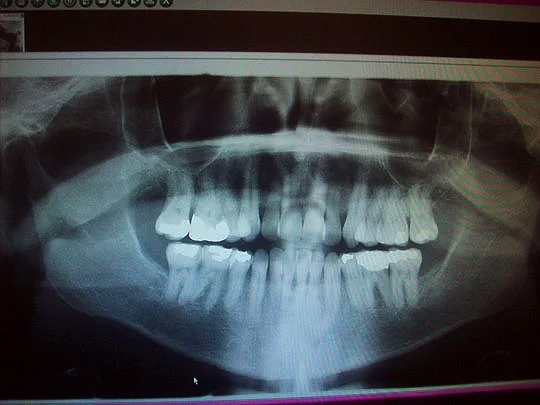

Let the x-rays begin!

And here they are, wow, it's kind of crowded inside of my mouth!